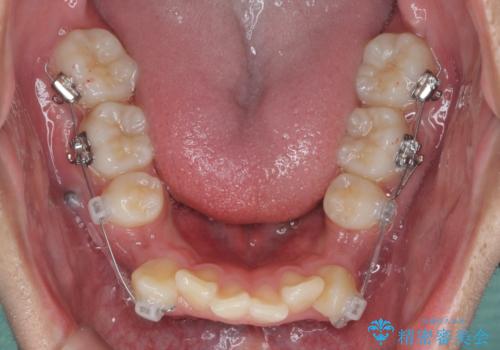

- 前歯のがたつきが原因で歯ブラシしづらい、見た目を改善したい!と矯正治療を希望され来院されました。

スペースの不足が見られるため、小臼歯の4本抜歯を行いマルチブラケットを用いた矯正治療を計画します。

噛み締めが強く、治療に時間がかかりましたが矯正治療の仕上がりに満足いただくことができました。